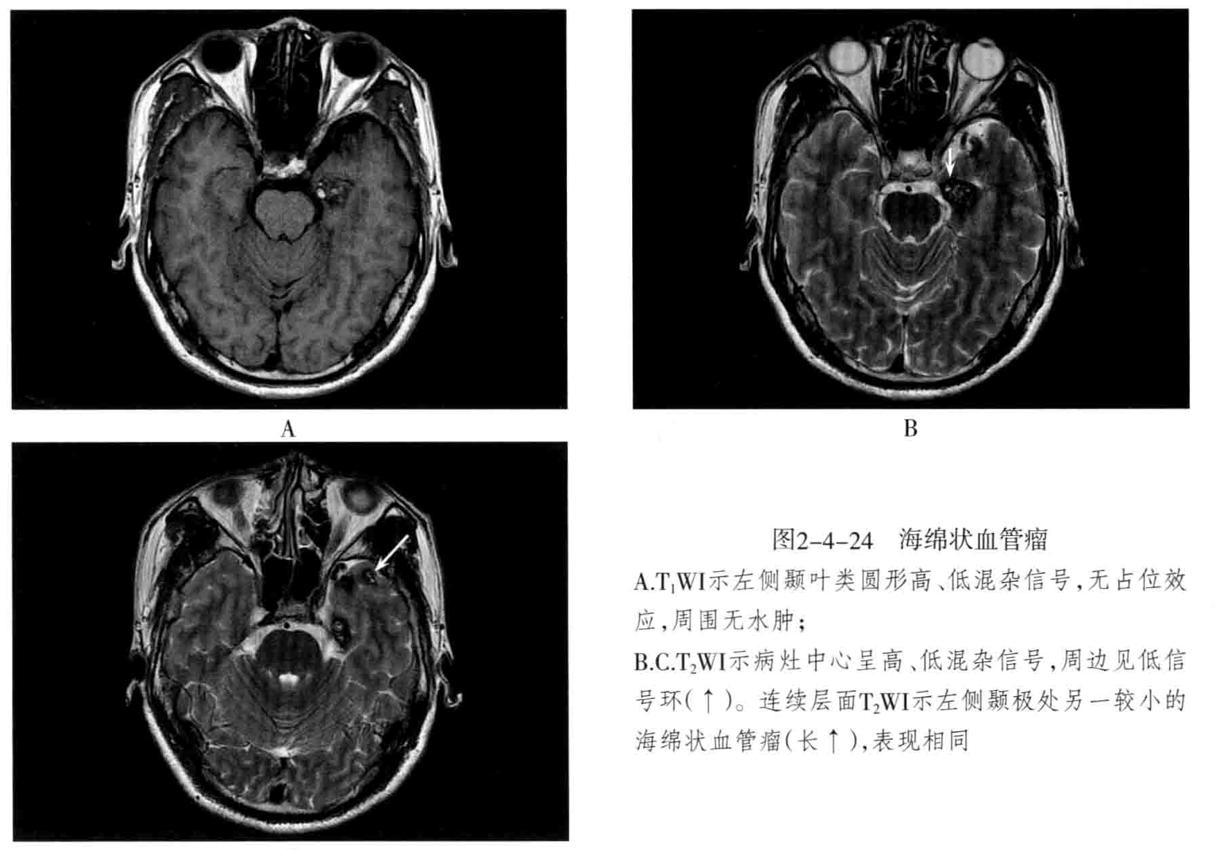

- 脑静脉性血管瘤 极为少见。静脉性血管瘤是一种组织上完全由静脉成分构成的脑血管畸形,任何年龄均可见,病理特点为许多放射状排列的扩张髓静脉连接成一条或多条扩张的经皮质或室管膜下引流静脉,最后汇入静脉窦。常发生于 额叶及小脑,以第四脑室周围多见 ,常伴发其他血管畸形,最常见为海绵状血管瘤。

- CT表现:平扫显示不清,周围无脑水肿,有时可见出血等改变,CTA典型表现为额叶或小脑许多细小髓静脉放射状汇入一条或几条引流静脉,最后汇入静脉窦,呈“水母头征”。

- MRI表现:可因病灶大小及血流速度不同而在MRI上呈多种信号,T1WI、T2WI多呈流空信号,少数由于血流缓慢也可呈略高信号,FLAIR呈低信号。增强后髓静脉及引流静脉明显强化,典型者呈“水母头征”,引流静脉可走向脑表面而引流至静脉窦,或走向脑室引流至室管膜静脉。MRV可显示引流静脉及其引流情况,但不显示髓静脉,SWI序列对本病显示很敏感。病灶周围无脑水肿表现,有时可见出血。

- 鉴别诊断:动静脉畸形:由供血动脉、畸形血管团、粗大引流静脉构成。海绵状血管瘤:多可见不同时期反复出血的产物,周围脑实质多有脑萎缩改变,MRI呈爆米花样改变为特征,周边见含铁血黄素环,增强后轻度或无去强化。